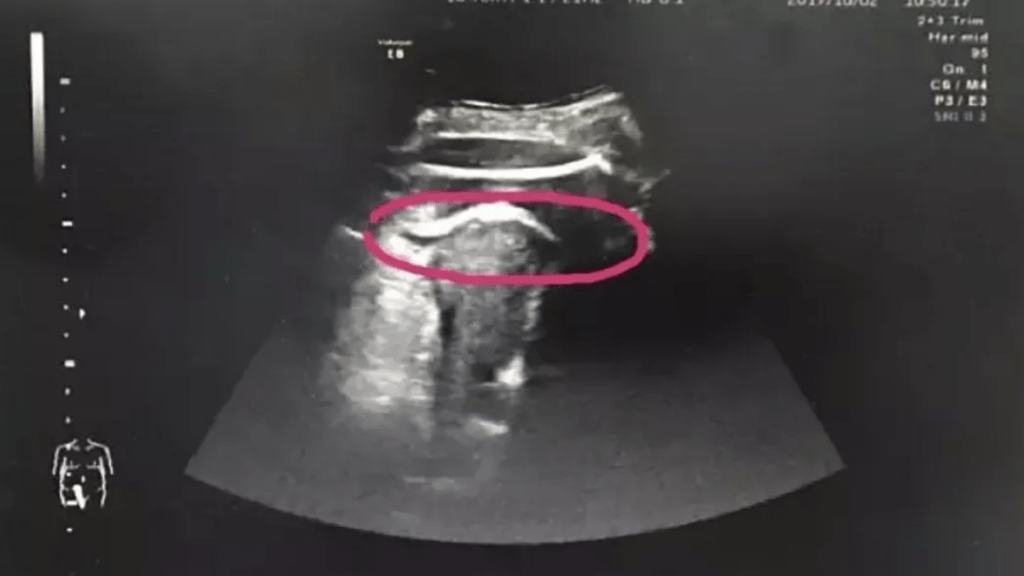

Zhang se había sometido a una cirugía en 2016 para extirpar fibromas uterinos que son tumores no cancerosos que se forman en el útero de algunas mujeres. Estos tumores están compuestos de tejido muscular y fibroso y pueden variar en tamaño, desde pequeños y apenas perceptibles hasta grandes y dolorosos. Algunas mujeres pueden tener un solo fibroma, mientras que otras pueden tener múltiples fibromas. Debido a esto, los médicos sospecharon de una rotura cicatricial del útero, lo que fue confirmado mediante una ecografía.

Después del diagnóstico, Zhang fue llevada al quirófano de inmediato, donde se descubrió que las piernas del feto estaban saliendo a través de una rasgadura de 7 centímetros en su útero. Los médicos explicaron que la cirugía anterior de la mujer dejó tejido cicatricial en su útero, lo que aumentó el riesgo de una rotura uterina.